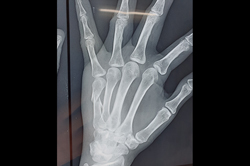

Mallet Finger